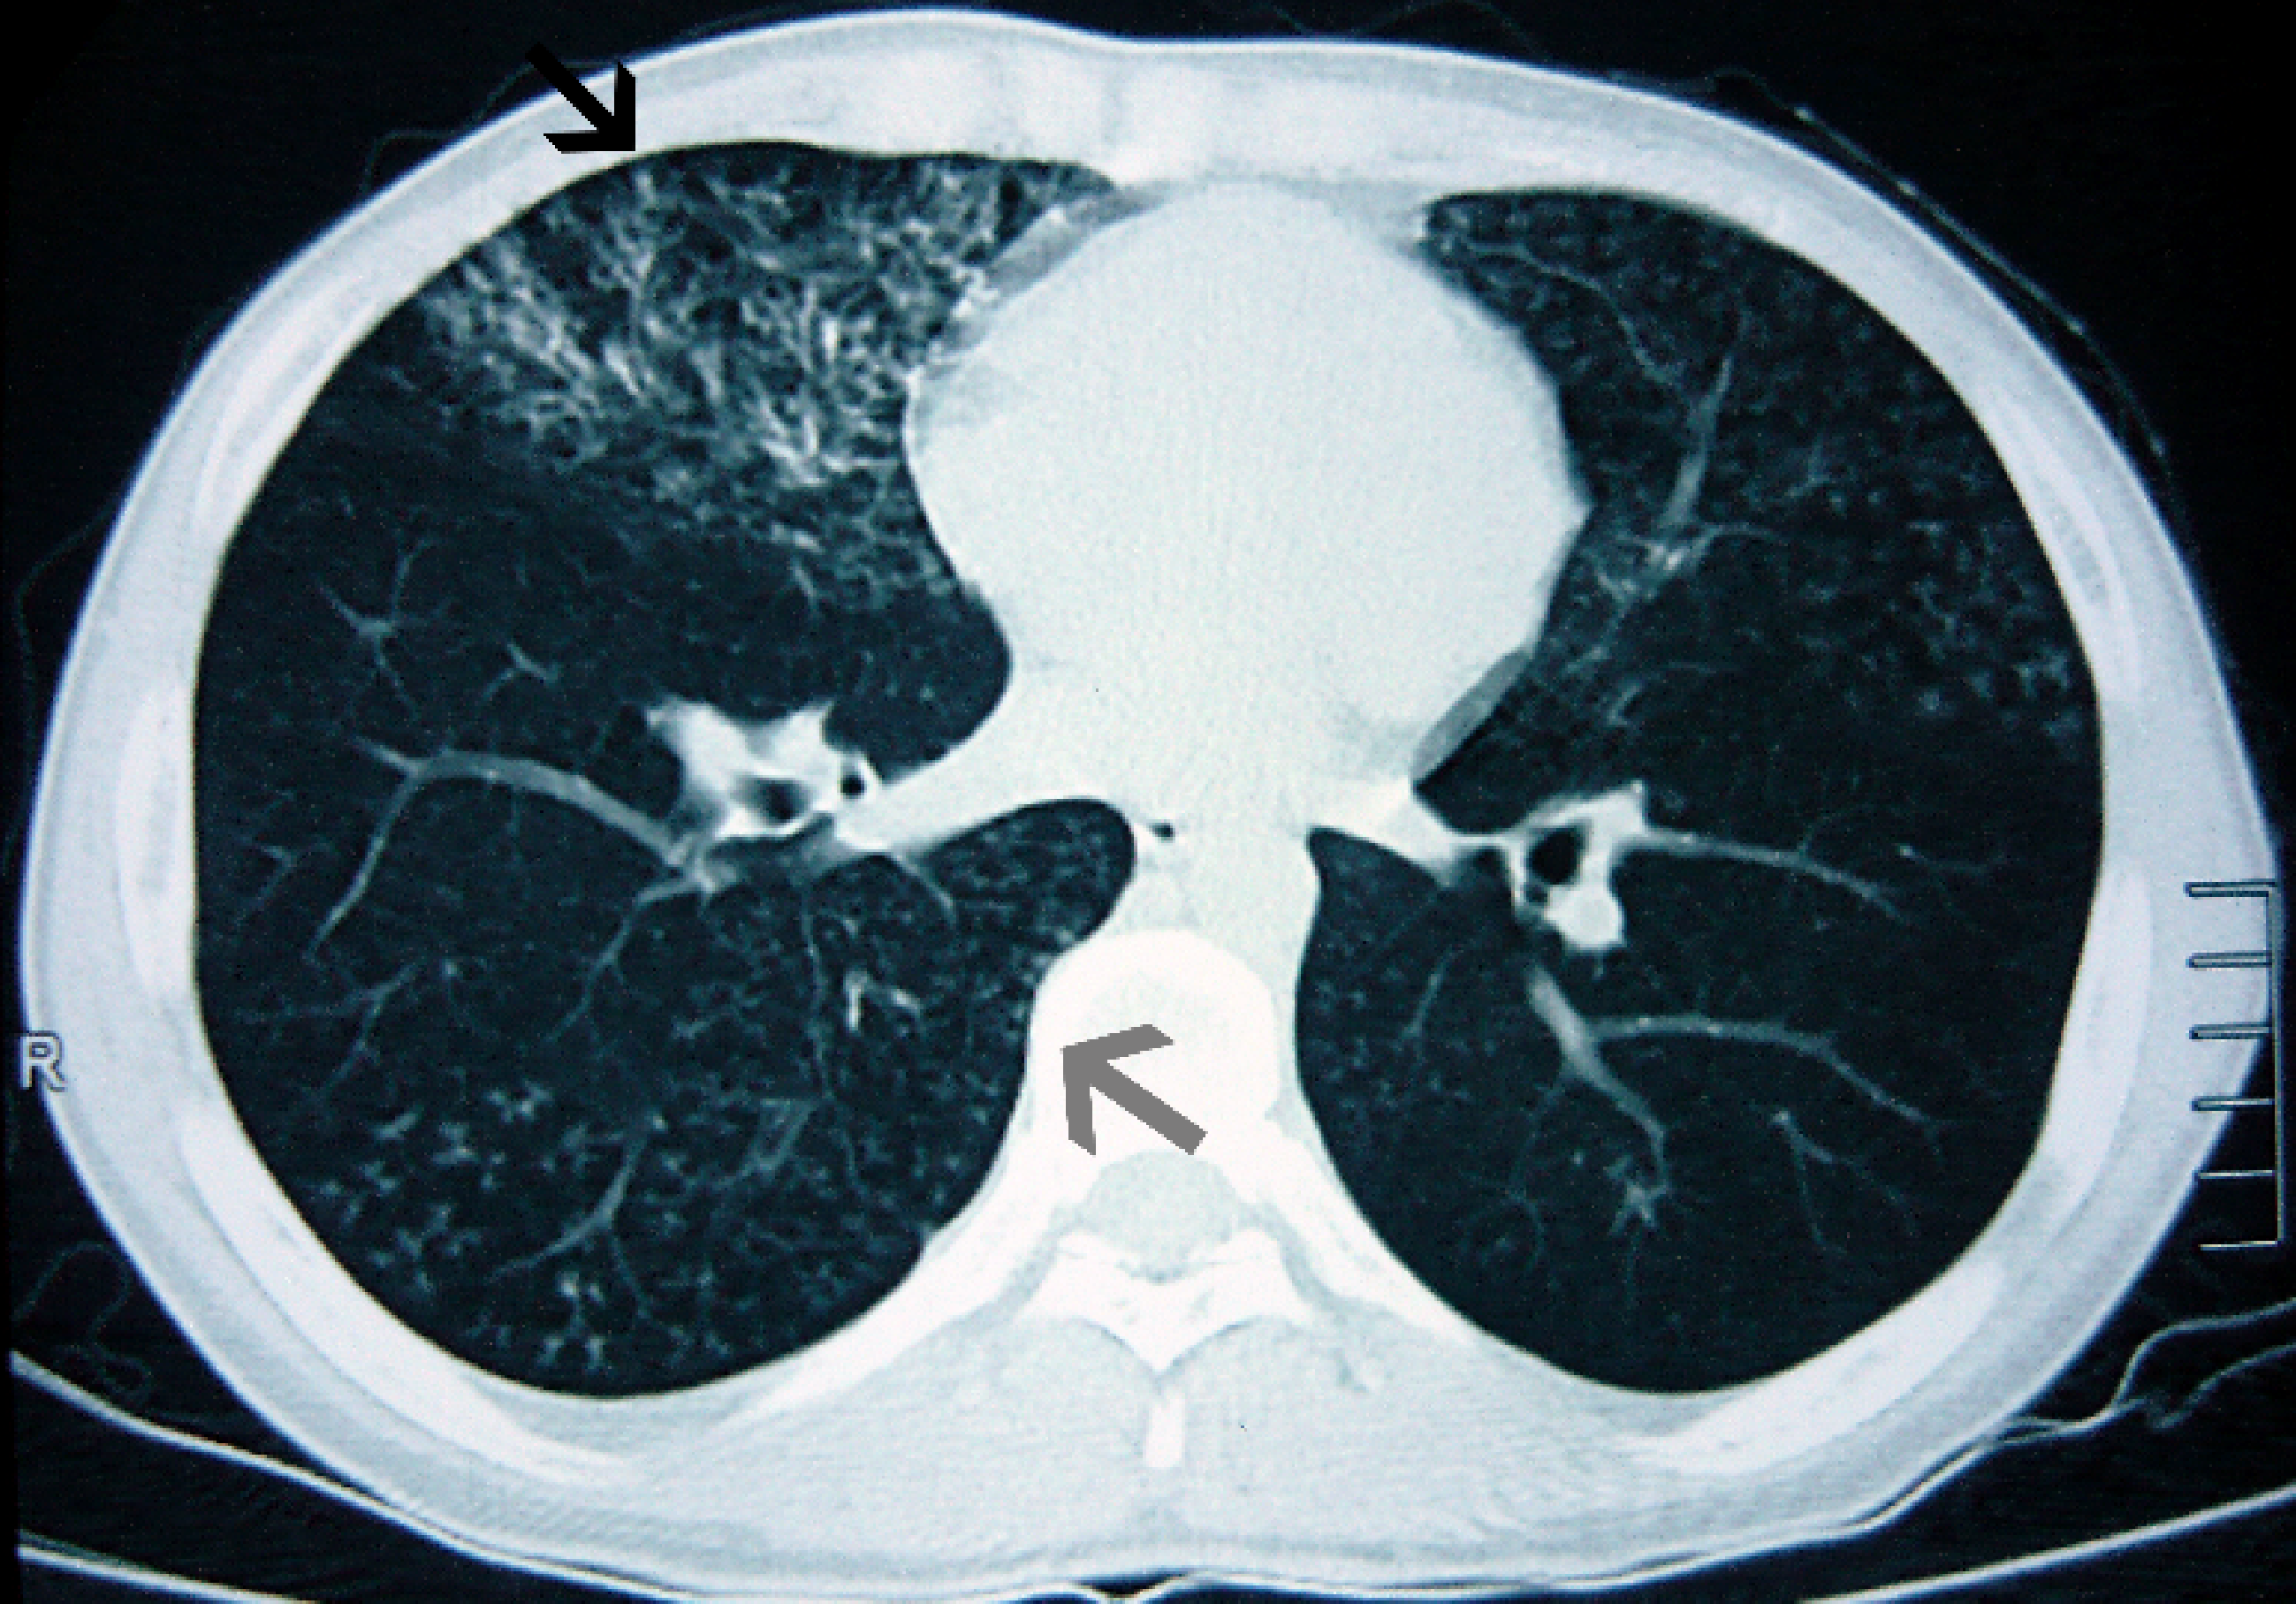

Chun Bian, Xinyue Zhao, Yaping Liu, Minjiang Chen, Shuying Zheng, Xinlun Tian, Kai-Feng Xu

Neurofibromatosis (NF) is a genetic disease in which the lungs are rarely involved. However, in NF cases with lung involvement, chest computed tomography may show bilateral basal reticulations, apical bullae, and cysts without bronchiectasis. Herein, we report a patient diagnosed with NF on the basis of the results of genetic testing who presented with early-onset wet cough and bronchiectasis. Considering the differential diagnosis of bronchiectasis combined with his early-onset wet cough, sinusitis, and sperm quality decline, we considered the possibility of primary ciliary dyskinesia (PCD). Further electron microscopy analysis of cilia and identification of homozygous mutations in the RSPH4A gene confirmed the diagnosis of PCD. Therefore, for patients with NF, when an image change exists in the lungs that does not correspond to NF, the possibility of other diagnoses, including PCD, must be considered.